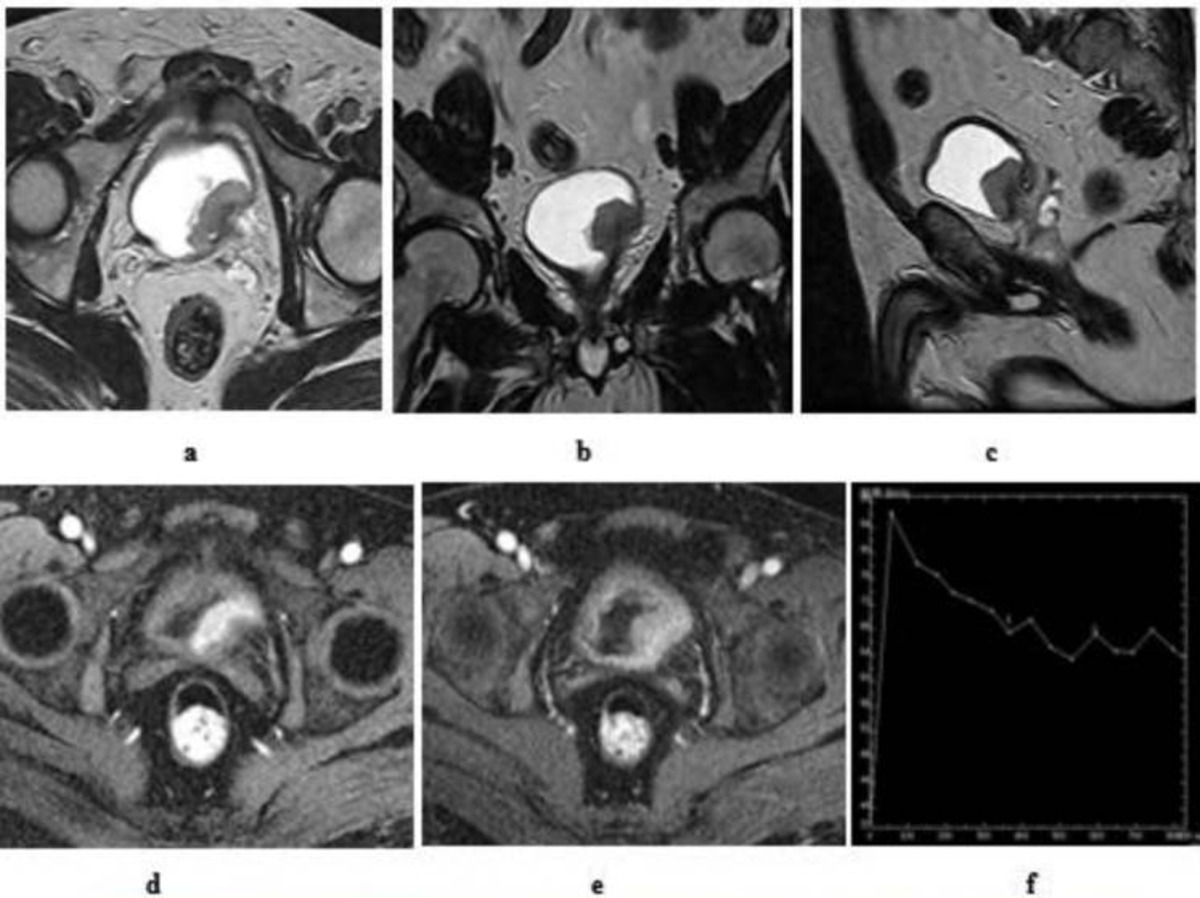

Multiparametric MRI (mpMRI), which incorporates functional sequences like diffusion-weighted imaging (DWI) and dynamic contrast-enhanced imaging, is especially effective for staging and evaluating response to treatment2. Bladder MRI is safe, uses no ionising radiation, and may also identify subtle abnormalities or infiltrative disease missed by other modalities.

Several specialised MRI scan types are routinely used in bladder cancer detection, each providing unique information to help diagnose, stage, and plan treatment for bladder tumours:

This sequence highlights the different layers of the bladder wall, making it easier to see how deep a tumour has grown. Tumours usually appear brighter than normal muscle, and this type of scan is important for assessing whether the muscle layer is still intact or disrupted by cancer31,32.

DWI assesses how water molecules move within tissues. Tumours tend to restrict water movement, so they stand out as areas of restricted diffusion31–33. This helps in identifying and confirming suspicious lesions, even when they are small or subtle.

This is a map derived from DWI that provides a numerical value to help separate aggressive cancers (which have lower ADC values) from less aggressive tumours. Lower ADC suggests increased tumour cell density31,32.

DCE captures images over time after a contrast dye is injected. Malignant tumours often soak up the dye earlier than normal bladder wall tissue, a sign of abnormal blood vessels31,32,34. This helps distinguish cancer from benign tissue and is useful for staging and treatment monitoring.